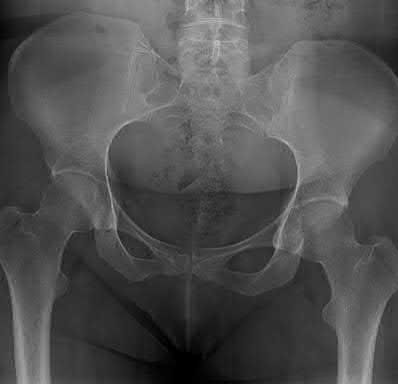

A poly-trauma patient presents hemodynamically unstable with an anteroposterior compression (APC-III) pelvic ring injury. A circumferential pelvic binder is requested to reduce pelvic volume and control hemorrhage. To be anatomically effective, the binder must be centered precisely over which of the following landmarks?

Explanation